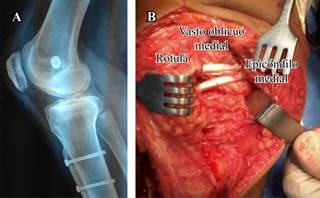

El procedimiento es completado con una reconstrucción del ligamento patelofemoral medial utilizando un injerto de tendón semitendinoso, el cual se tuneliza a través de la rótula y se fija en el punto de isometría femoral según Schottle (Figura 6).15

Figura 6: A) Tornillo interferencial estabilizando la reconstrucción del LPFM con injerto autólogo de tendón semitendinoso. B) Imagen intraoperatoria del injerto de semitendinoso atravesando el borde rotuliano medial a través de túneles transóseos) y una plástica del vasto oblicuo medial (plástica de Insall-modificada).

Realizamos una incisión recta longitudinal en la piel en la cara anterior de la rodilla desde el margen superior de la rótula hasta la articulación femorotibial mientras la rodilla se encuentra en 90o de flexión. Luego, la rodilla se coloca en extensión y se realiza una artrotomía siguiendo las fibras del vasto oblicuo medial, exponiendo 1-2 cm el borde medial de la rótula.